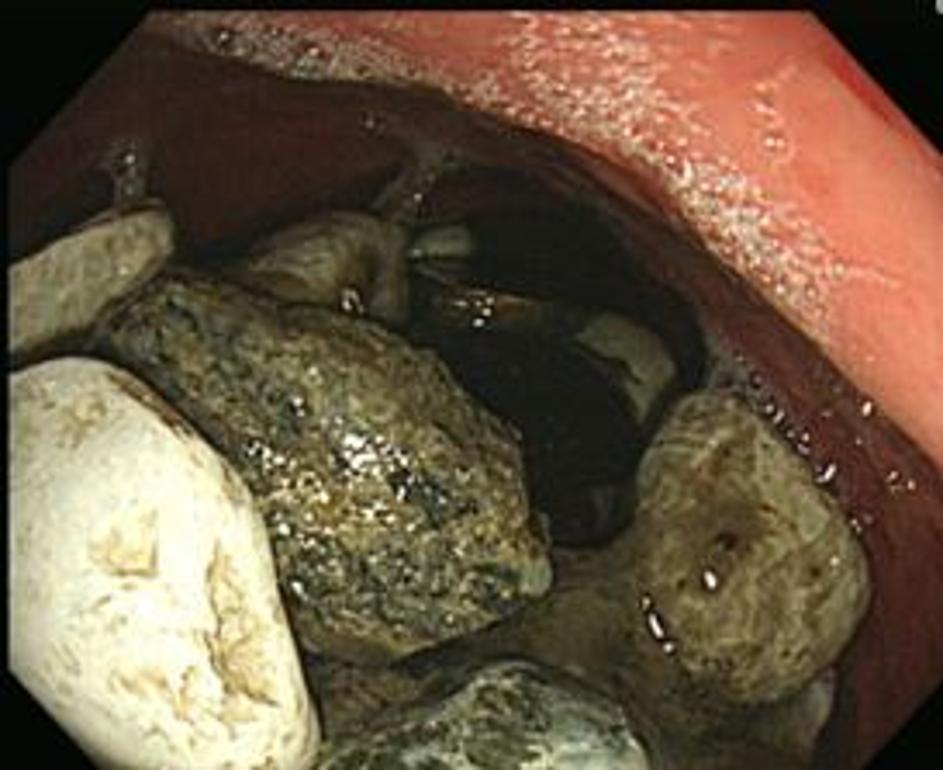

Gastroskopija American Journal of Medical Case Reports Gastroskopija